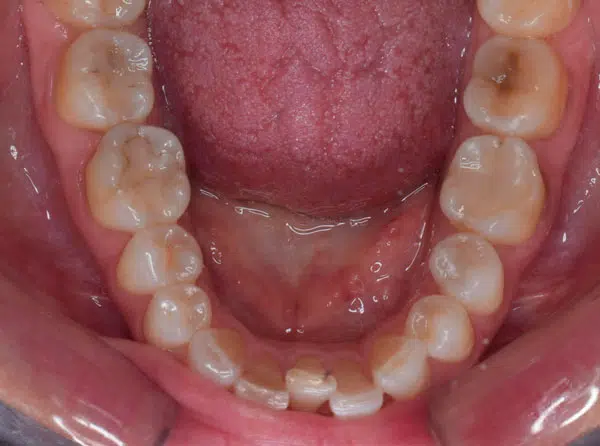

Ofrecemos tratamientos de ortodoncia diseñados para cada paciente de acuerdo a sus necesidades, desde la ortodoncia convencional con brackets metálicos o estéticos (zafiro) hasta ortodoncia sin brackets (alineadores) para lo cual contamos también con scanner intraoral para tener un diagnóstico ágil y preciso de cada caso.